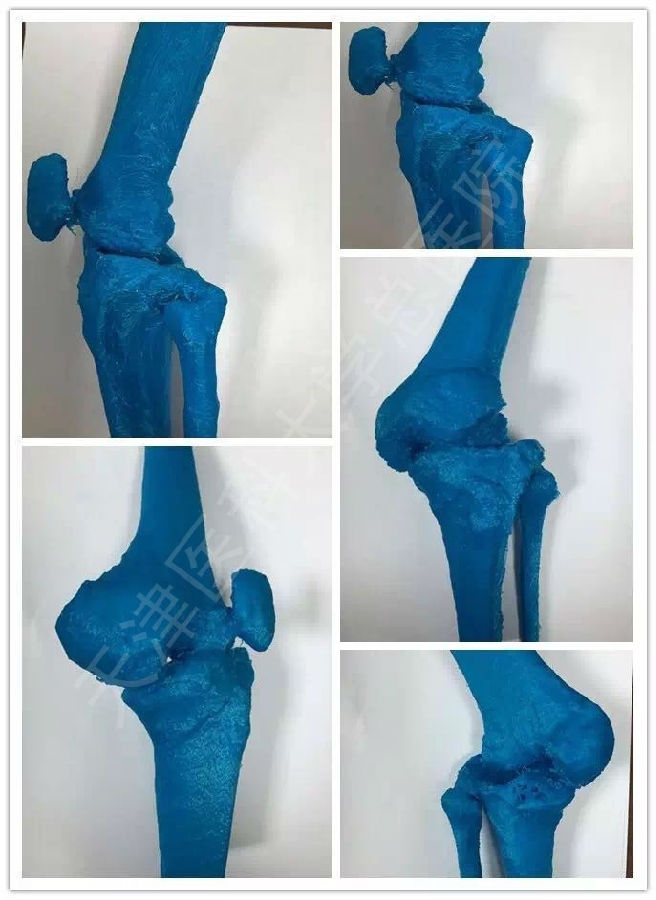

据骨外科李晖主任医师介绍:针对患者的严重关节畸形,天津医大总医院骨外科联合天津市骨研所应用患者CT数据利用3D打印技术,在术前1:1精确构建了患者膝关节的实体模型,并依此几经推敲制定患者的最适手术方案,在手术前应用Workshop模拟演练手术全程以完备细节。

术前Workshop演示手术,完备细节